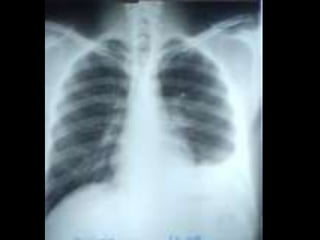

• C’est un téléthorax de face objectivant une opacité de tonalité

hydrique siégeant au niveau du champ pulmonaire inférieur

gauche, de forme ovalaire, mesurant 5cm de grand axe, de plage

hétérogène par la présence de broncho gramme, de limites plus

ou moins nettes et les contours sont irréguliers.

• En appliquant le signe de la silhouette, l’opacité n’efface pas le

bord gauche du médiastin donc elle est de topographie

postérieure. Ailleurs on note une opacité hilaire gauche

irrégulière. L’index cardio-thoracique est normal, les culs de sac

pleuraux sont libres, pas de lésions osseuses visibles.

• Conclusion : syndrome de comblement alvéolaire évoquant un

cancer broncho-pulmonaire, métastase pulmonaire unique

Diagnostic différentiel : abcès du poumon, tumeur bénigne.

• CAT : TDM thoracique, échographie abdomino-pelvienne et

scintigraphie osseuse Fibroscopie bronchique